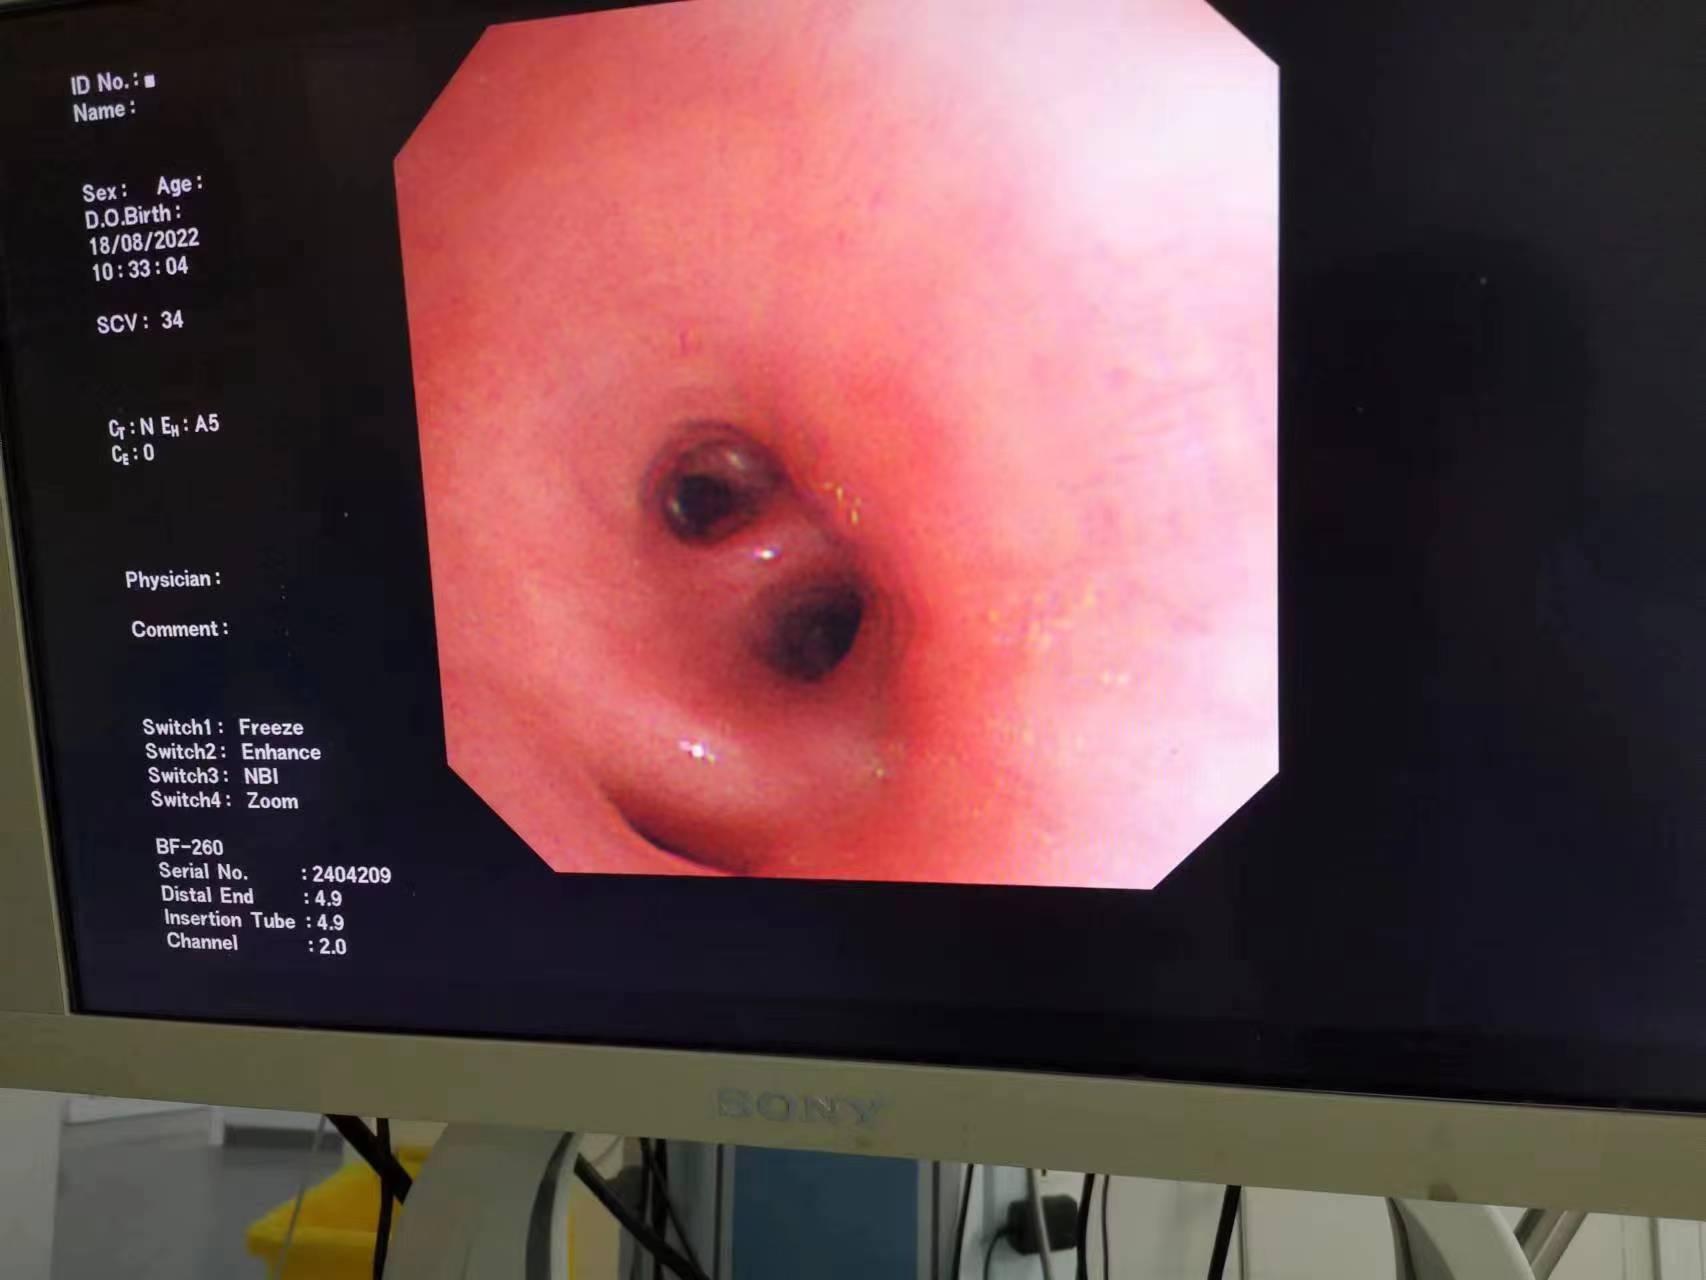

在亚星手机版官方登录内镜中心,有间诊疗室一改其他诊室的安静氛围,孩子哭喊声陆续传来。这里是小儿支气管镜诊疗室。时间来到2022年8月12日,4岁的小项因持续发热、咳嗽长达5天,......